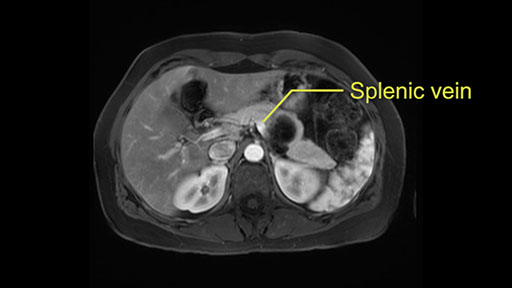

Tumor proximity to splenic vein

Other slowing down moments with this procedure include dissection of the splenic vein and splenic artery. These are technically challenging moments and important moments where care needs to be taken. Not only to avoid bleeding and injury to the vessels but also to ensure an adequate margin.

The lesion itself is quite adjacent to and abuts the splenic vein and therefore we need to anticipate that these two structures will be intimately related and possibly impossible to separate between the two.

The second slowing down moment or consideration I give to a distal pancreatectomy is the anatomy of the portal vein and the splenic artery. And so I look here and the anatomy is pretty straightforward. The splenic vein comes off normally and runs behind the pancreas and I can see the artery superior to that, again coming off in a normal manner from the celiac axis. So those two things, the portal vein and the splenic artery will be taken normally in this procedure.

So first step that we do: mobilize the splenic flexure first to visualize Gerota’s fascia and that would help bring down the colon and expose the pancreatic tail. So now that the pancreas is visible, division of the gastrocolic ligament will come into view. And a window can be created at the inferior edge of the pancreas to slowly lift the inferior edge to expose the splenic vein behind. This is the slow-down moment that I am talking about because the MR shows that there could be contact with the cyst. It’s important to know that to avoid perforation, to avoid rupture of the cyst, because we need to avoid touching the cyst, it is quite a size of 4.3 about 4cm.

I think the splenic vein, once I have slowly teased it off from the cyst and from the retropancreatic parenchyma, I would put a vessel loop around it to serve as a traction. So once you have the vessel loop or probably umbilical tape, to retract or pull the pancreatic parenchyma while we slowly tease it off and try to move superiorly to be able to expose the splenic artery. That is again another slow-down moment because sometimes we think that it is the splenic artery at the superior edge of the pancreas, but it could also be the hepatic artery as it branches from the celiac artery.